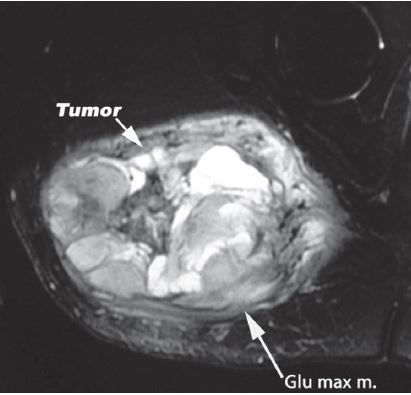

It is a procedure that involves removing a tumor of the gluteus maximus, also known as the buttock. This is done while preserving the surrounding bone and soft tissues.